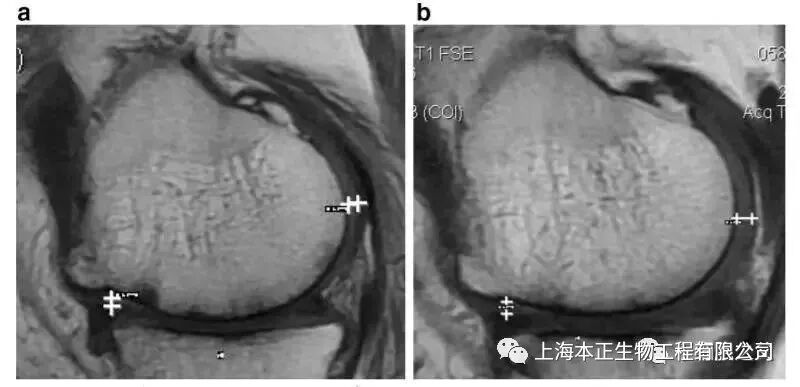

▲如上图所示,左图为治疗前,右图为治疗后,白色“+”处示意软骨增厚。

治疗结果治疗后,2年后WOMAC评分也得到改善。6分钟内步行距离也显著增加。60%的病人的软骨体积增加。